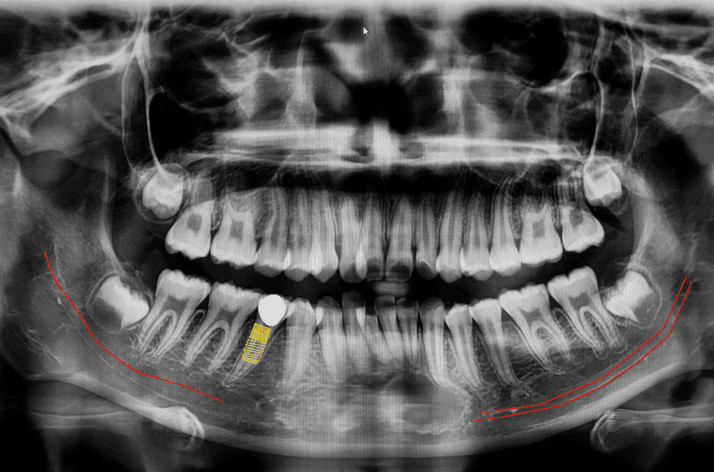

Panoramic X-Ray:  This is a type of sizeable dental X-ray that requires a separate machine. The X-ray provides a detailed image of all the teeth in both lower and upper arches, along with the bone and supporting structures. They are usually used for extensive dental work like multiple extractions, braces, dental implants, etc.